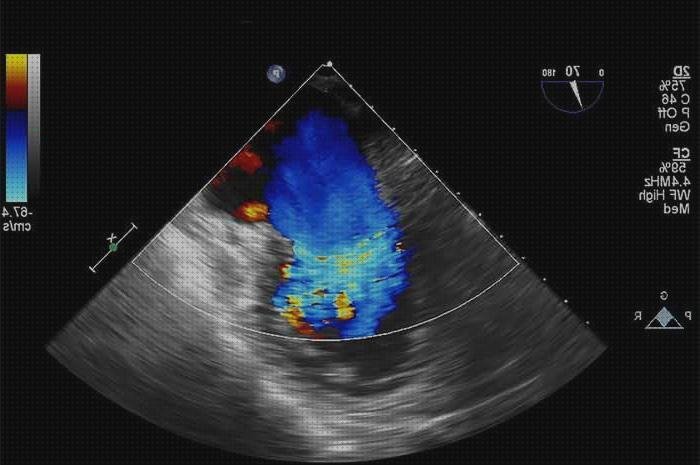

Una ecografía doppler es una investigación por imágenes que emplea ondas de sonido para exhibir la circulación de la sangre por los vasos sanguíneos. Las ecografías comunes también utilizan ondas de sonido para hacer imágenes de construcciones internas del cuerpo, pero no pueden exhibir la sangre en circulación.

La ecografía doppler funciona buscando ondas sonoras que se demuestran en objetos en movimiento, como los glóbulos colorados. Esto se le conoce como producto doppler.

La tecnología que hace uso de esta misma electrónica es el ultrasonido, que es seguro e leve. Colocando la cabecera de la máquina sobre la epidermis, se producen ondas sonoras y crean una imagen en el monitor para que el médico visualice el estado de la zona, pudiendo valorar el paso de la sangre. Esta máquina no hace uso de radiación por lo que no hace ninguna complicación al paciente.

Otra de las cualidades positivas de la repercusión doppler es la posibilidad que da de análisis de las imágenes del interior de los órganos, venas y arterias en tiempo palpable. Éstas se hacen ver en la pantalla durante la ejecución de la prueba, cuestión atractiva de cara al futura de las intervenciones quirúrgicas.

El eco doppler es una prueba no invasiva ni dolorosa que usan los operadores vasculares para contar el flujo de la sangre en los vasos sanguíneos. ésto se logra realizando retroceder las ondas sonoras de mayor continuidad en los glóbulos rojas. Esta prueba es un tipo de ecografía que nos deja establecer afecciones como las posteriores:

Este dispositivo le deja al operador vascular llevar a cabo un peritaje del estado de las venas y varices de los pacientes para lograr tener un dictamen claro del estado y así lograr determinar el proceso que el enfermo requiere, en base a la evaluación.

Permite visión del corazón y sus válvulas inquietos para identificar si la fuerza con la cual se contrae corazón es la correcta.

Arroja imágenes del flujo de las arterias detectando posibles patologías vinculadas con la circulación en estas como estrecheces o estrechamiento.